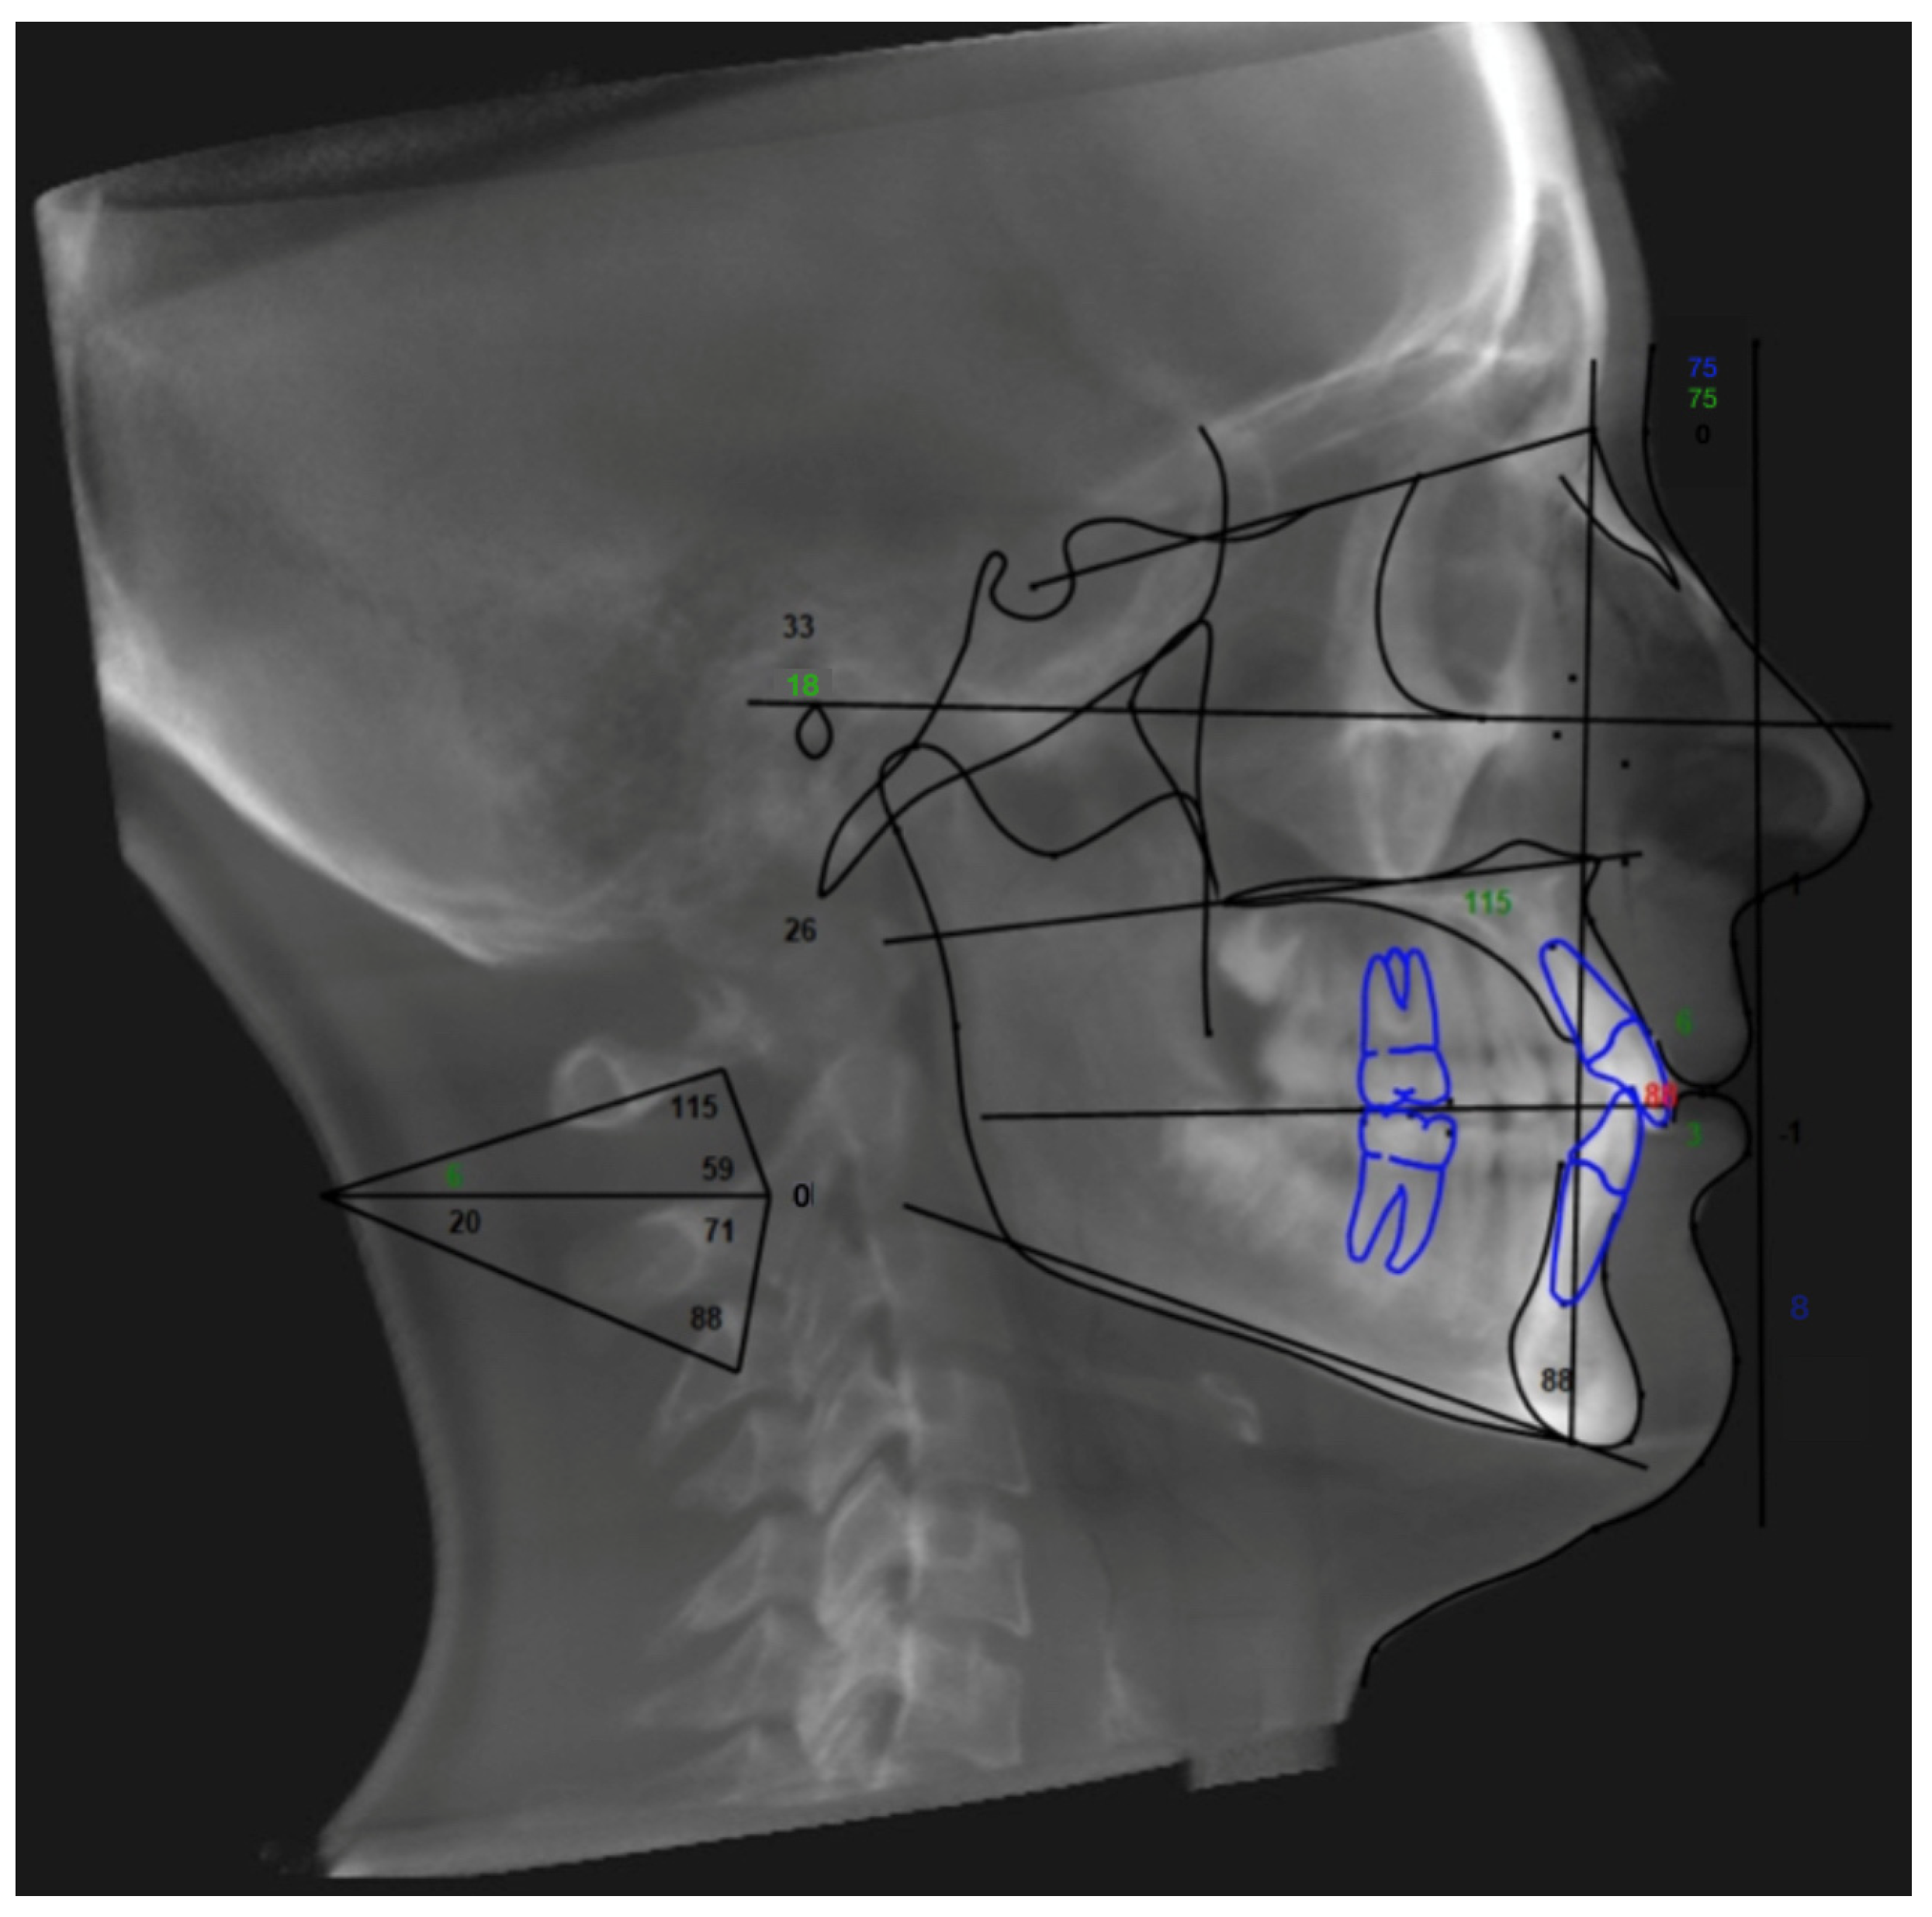

2. Materials and Methods